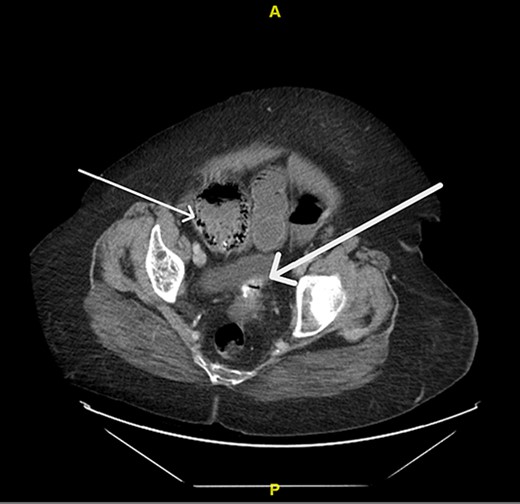

Upon evaluation, the patient was found to have white blood cells 20.1 (4–10.9), with unremarkable vitals and no signs of peritonitis on examination. Computerized tomography (CT) abdomen/pelvis revealed a large bowel obstruction with pneumatosis intestinalis of the right colon secondary to a sigmoid mass (Fig. 1). Upon surgical review of the images, the patient’s CT also showed a left-sided intercostal hernia containing loops of large bowel that was not initially reported by the radiologist (Fig. 2). The mechanism of this was unclear; however, it has been hypothesized that it could be a result of a combination of severe cough related to patient’s recent pneumonia and underlying COPD, or trauma to the left chest wall allegedly sustained at the previous facility.

Pneumatosis intestinalis of the right colon (thin arrow) and sigmoid mass (thick arrow).